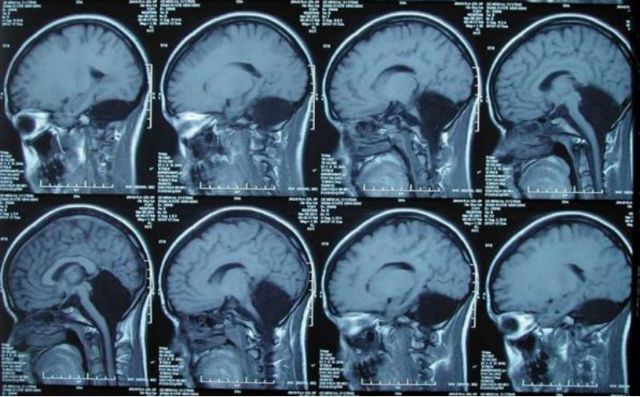

Οι γιατροί διεξήγαγαν αξονική τομογραφία στην ασθενή και εντόπισαν την πηγή του προβλήματος αμέσως – έλειπε ολόκληρη η παρεγκεφαλίδα της. Το σημείο στο οποίο έπρεπε να βρίσκεται η παρεγκεφαλίδα δεν έφερε άλλους ιστούς αλλά ήταν γεμάτο με εγκεφαλονωτιαίο υγρό, το οποίο λειτουργεί ως «ασπίδα» του εγκεφάλου ενάντια στις ασθένειες.

Η παρεγκεφαλίδα, που ορισμένες φορές αποκαλείται «μικρός εγκέφαλος», βρίσκεται κάτω από τα δύο ημισφαίρια του εγκεφάλου. Στην όψη είναι διαφορετική από τον υπόλοιπο εγκέφαλο καθώς αποτελείται από πολύ μικρότερα και πιο συμπαγή στρώματα ιστών. Αντιπροσωπεύει περίπου το 10% του συνολικού όγκου του εγκεφάλου αλλά περιέχει το 50% των νευρώνων του.

Το κύριο καθήκον της παρεγκεφαλίδας είναι να ελέγχει τις εκούσιες κινήσεις και την ισορροπία ενώ επίσης πιστεύεται ότι εμπλέκεται στην εκμάθηση κινήσεων και στην ομιλία. Προβλήματα στην παρεγκεφαλίδα μπορούν να οδηγήσουν σε σοβαρή ψυχική και νοητική διαταραχή, σε διαταραχές της κίνησης, σε επιληψία αλλά και σε εν δυνάμει θανατηφόρα συσσώρευση υγρού στον εγκέφαλο.